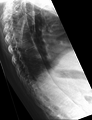

Fracture of the T5 and C7 vertebra due to trauma in a person with ankylosing spondylitis as seen on a CT scan

Prognosis is related to disease severity.[7] AS can range from mild to progressively debilitating and from medically controlled to refractory. Some cases may have times of active inflammation followed by times of remission resulting in minimal disability while others never have times of remission and have acute inflammation and pain, leading to significant disability.[7] As the disease progresses, it can cause the vertebrae and the lumbosacral joint to ossify, resulting in the fusion of the spine.[24] This places the spine in a vulnerable state because it becomes one bone, which causes it to lose its range of motion as well as putting it at risk for spinal fractures. This not only limits mobility but reduces the affected person's quality of life. Complete fusion of the spine can lead to a reduced range of motion and increased pain, as well as total joint destruction which could lead to a joint replacement.[25]

Osteoporosis is common in ankylosing spondylitis, both from chronic systemic inflammation and decreased mobility resulting from AS. Over a long-term period, osteopenia or osteoporosis of the AP spine may occur, causing eventual compression fractures and a back "hump".[26] Hyperkyphosis from ankylosing spondylitis can also lead to impairment in mobility and balance, as well as impaired peripheral vision, which increases the risk of falls which can cause fracture of already-fragile vertebrae.[26] Typical signs of progressed AS are the visible formation of syndesmophytes on X-rays and abnormal bone outgrowths similar to osteophytes affecting the spine. In compression fractures of the vertebrae, paresthesia is a complication due to the inflammation of the tissue surrounding nerves.